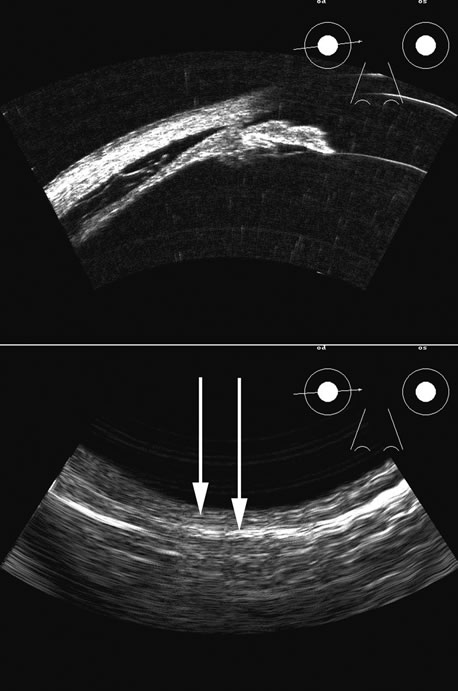

Fig. 6. Hypotony of the eye generally is easily diagnosed by a separation of the ciliary body from the sclera. We have noted several types of such separation, such as tractional, primary (idiopathic), and dehiscence secondary to iridodialysis or scleral perforation, as in filtration procedures. In our series, greater than two clock hours of separation is typical of hypotony. The lower figure shows a concomitant thickening of the retina-choroid complex, also seen in hypotony (arrows). Long-standing hypotony typically has a shortened globe and possible retinal or choroidal separation.

Hypotony is easily diagnosed by direct measurement of intraocular pressure, but the underlying cause is difficult to evaluate.11 High-frequency ultrasound scans can easily reveal separation of the ciliary body and the sclera. This allows different forms of hypotony to be determined—for example: tractional with membrane attached; primary as idiopathic, often inflammatory or hemorrhagic; and dehiscence secondary to iridodialysis or scleral perforation (Fig. 6).